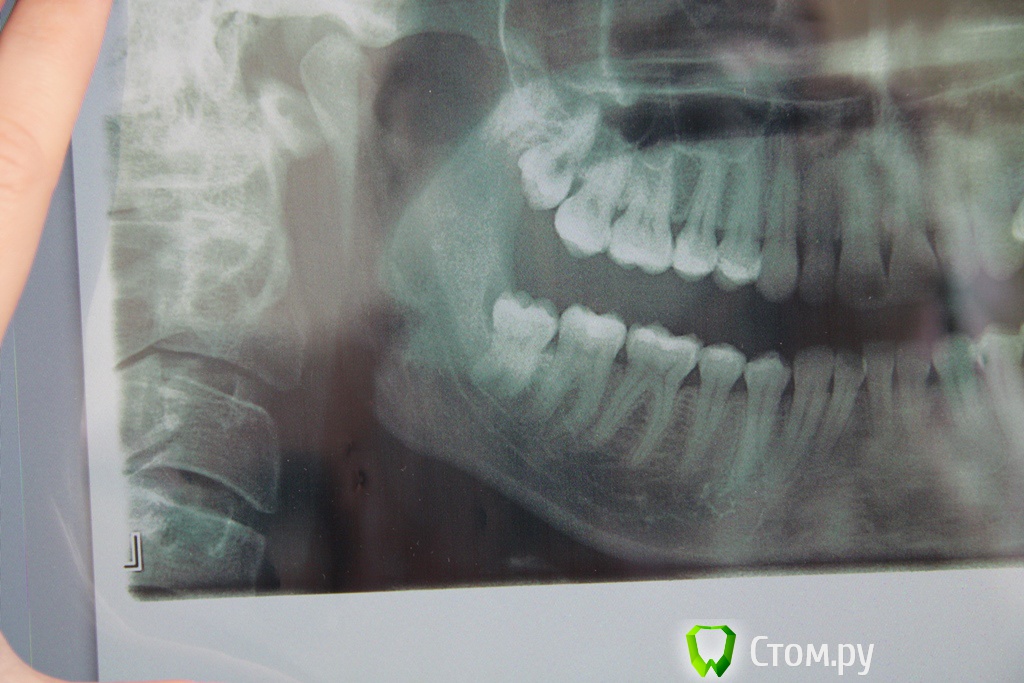

red_butler Опубликовано 12 апреля, 2014 Поделиться Опубликовано 12 апреля, 2014 (изменено) 1. Зуб сложным не выглядит, но это только плоский снимок, действительность иногда иная. Если с учётом анестезии, то бывает и более часа2. Резинка называется дренаж, иногда используется3. Бывает, перед травматичными вмешательствами4. При адекватной анестезии, боли быть не должно, но бывают исключения. Было больно, или очень неприятно?Как вариант дальнейшие вмешательства проводить под седацией Изменено 12 апреля, 2014 пользователем red_butler Ссылка на комментарий

rivezico Опубликовано 16 апреля, 2014 Поделиться Опубликовано 16 апреля, 2014 по снимку легкий, но на деле может быть сложным Ссылка на комментарий

Цунами Опубликовано 5 мая, 2014 Автор Поделиться Опубликовано 5 мая, 2014 Здравствуйте!Скажите пожалуйста, обязательно ли удалять 18 и 48 зубы?Мне 35 лет, может ли 48 зуб прорезаться полностью? 18 зуб меня вообще не беспокоит, прорезался полностью давно, зубной щёткой прочищаю хорошо. Может и не нужно их трогать. Ссылка на комментарий

red_butler Опубликовано 6 мая, 2014 Поделиться Опубликовано 6 мая, 2014 Удалил бы оба 1 Ссылка на комментарий

faity Опубликовано 7 мая, 2014 Поделиться Опубликовано 7 мая, 2014 Удалил бы оба+1зачем ждать боли? Ссылка на комментарий